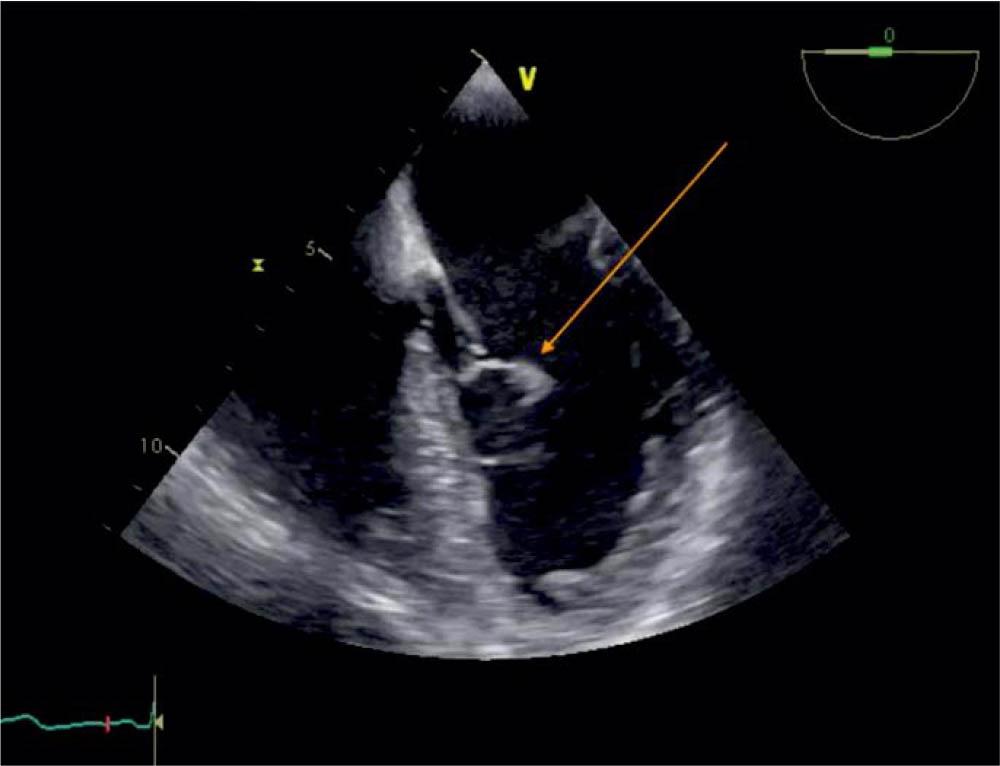

Figure 4

TEE 0 degrees, visualization of the blood cyst (arrow) attached to the AML.